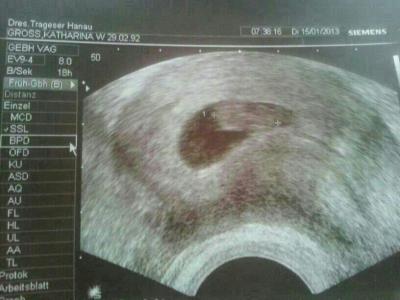

Huhu Mädels, War eben beim fa. Also ist alles ok. Baby ist jetzt 1.5 cm Groß :) Hat schon gestrampelt :) Wurde zwei Tage vordatiert. Bin heute 8+2! Nächsten Termin habe ich schon am 1.2 :) Wie sind so glücklich! Bildchen ist anbei :) LG Ina :) Achso habe heut auch ein bv bekommen das werde ich Morgen gleich auf der Arbeit abgeben :)

Bild zu FA Termin Bericht! - Forum für August - Mamis